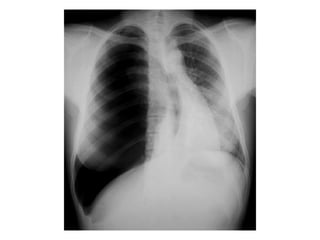

Chest x ray